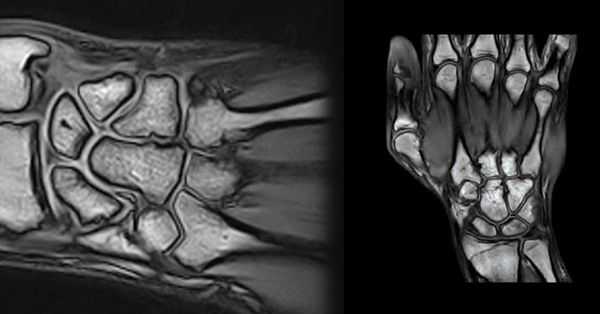

Первая из 20 последовательных Т1-взвешенных томограмм запястья в продольной проекции с направлением срезов от локтевой (медиальной) стороны к лучевой (латеральной). Сухожилие ЛоРЗ пересекает дистальный отдел локтевой кости в локтевой борозде ЛоРЗ. Мышца, отводящая мизинец—самая медиальная и передняя мышца гипотенара. Гороховидно-пястная связка соединяет гороховидную кость с V пястной костью. Она прилежит к гороховидно-крючковидной связке (следующая томограмма). Хорошо виден гороховидно-трехгранный суставной карман. Мышцы гипотенара менее прочные в области отхождения их от удерживателя сгибателей. Сухожилие локтевого сгибателя запястья прикрепляется к гороховидной кости. Локте-трехгранная связка отходит от ладонной лучелоктевой связки и прикрепляется к ладонной поверхности трехгранной кости. Локтевые нерв и артерия проходят в канале Гийона латеральнее и дистальнее гороховидной кости. Выступает крючок крючковидной кости. Треугольный хрящевой диск (ТХД) визуализируется в виде диска с низкоинтенсивным сигналом между головкой локтевой кости и трехгранной костью. Ладонная и тыльная лучелоктевые связки вместе с ТХД и прилежащими структурами образуют треугольный фиброзно-хрящевой комплекс. Внешние и внутренние связки иногда сложно выделить в качестве отдельных образований. Указатели направлены к визуализируемым связкам или месту возможного обнаружения связки. Тыльная межзапястная связка—основная связка, стабилизирующая тыльный отдел запястья, но визуализируется только на ограниченном участке. Сухожилия поверхностного и глубокого сгибателей пальцев проходят под горизонтально расположенным удерживателем сгибателей. Сухожилия разгибателя пальцев проходят через IV канал разгибателей и фиксируются удерживателем разгибателей. На ладонной поверхности можно увидеть пучки лучеладьевидно-локтевой и короткой лучеполулунной связок. На задней поверхности можно увидеть тыльную лучезапястную связку, отмечена область тыльной межзапястной связки. Характерный наклон в ладонную сторону дистального отдела лучевой кости обусловлен тем, что тыльный край лучевой кости расположен более дистально, чем ладонный (12°). Центральная ость запястья образована основанием III пястной кости, головчатой и полулунной костями, а также полулунной ямкой лучевой кости. Сухожилие разгибателя указательного пальца—самое латеральное сухожилие IV канала разгибателей. Сухожилие мышцы, противопоставляющей большой палец, на этом срезе отходит от удерживателя сгибателей. Срединный нерв расположен поверхностнее сухожилия длинного сгибателя большого пальца и глубже удерживателя сгибателей. Длинная лучеполулунная связка отходит от лучевой кости непосредственно латеральнее лучеладьевидной и короткой лучеполулунной связок. Сухожилие длинного разгибателя большого пальца лежит медиальнее бугорка Листера и в дистально-латеральном направлении на пути к большому пальцу пересекает сухожилия длинного и короткого лучевых разгибателей запястья. На этом срезе визуализируются сочленения трапециевидной, головчатой и ладьевидной костей между собой. Сухожилие длинного сгибателя большого пальца проходит под локтевым нервом непосредственно медиальнее сухожилия лучевого сгибателя запястья. Сухожилие короткого лучевого разгибателя запястья (КЛуРЗ) прикрепляется к основанию III пястной кости. Сухожилие лучевого сгибателя запястья проходит поверхностнее бугорка ладьевидной кости и прикрепляется к основанию II пястной кости. Лучеладьевидно-головчатая связка отходит от края ладонной поверхности лучевой кости. Сухожилие лучевого сгибателя запястья проходит поверхностнее бугорка ладьевидной кости и прикрепляется к основанию II пястной кости. Сухожилие короткого лучевого разгибателя запястья (КЛуРЗ) пересекает тыл запястья и прикрепляется к тыльной стороне основания III пястной кости. Наиболее латеральный отдел лучеладьевидно-головчатой связки иногда называют лучевой коллатеральной связкой. Сухожилие длинного лучевого разгибателя запястья (ДЛуРЗ) пересекает тыл запястья и прикрепляется к основанию II пястной кости. Лучевая артерия, поверхностная ветвь лучевого нерва и латеральная подкожная вена руки проходят через анатомическую табакерку, ограниченную костью-трапецией, ладьевидной костью и шиловидным отростком лучевой кости. Сухожилия длинной мышцы, отводящей большой палец и короткого разгибателя большого пальца, образуют ладонный край анатомической табакерки, а сухожилие длинного разгибателя большого пальца формирует ее тыльный край. Сухожилия длинной мышцы, отводящей большой палец и короткого разгибателя большого пальца, образуют дистальный край анатомической табакерки после соединения непосредственно дистальнее I запястно-пястного сустава. Лучевая артерия разветвляется и продолжается в дистальном направлении, образуя глубокую ладонную дугу. Сухожилия длинной мышцы, отводящей большой палец и короткого разгибателя большого пальца соединяются в месте прикрепления к основанию I пястной кости.